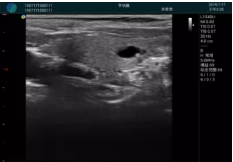

清晰顯示腺體內(nèi)低回聲快影,邊界清晰,包膜較光滑

確定進(jìn)針路徑并實(shí)時(shí)監(jiān)測(cè)抽吸針與腫塊位置關(guān)系

抽吸針進(jìn)入腫塊內(nèi)部進(jìn)行旋切

抽吸過程中可見腫塊明顯縮小,并根據(jù)腫塊位置改變針道位置

抽吸旋切后再進(jìn)行超聲復(fù)查,原腫塊區(qū)域未見殘留組織及出血

超聲以操作簡單、定位準(zhǔn)確、實(shí)時(shí)顯像、費(fèi)用低廉等優(yōu)勢(shì),而成為麥默通乳腺活檢治療乳腺腫塊最常見的引導(dǎo)手段,已逐步在各大醫(yī)院開展此類手術(shù)。

2、超聲的可視化操作,能準(zhǔn)確的顯示病灶的位置、最大徑,選擇合適的刀具,決定切口的位置和方向,避開血管、減少出血危險(xiǎn)并實(shí)時(shí)觀察乳腺病灶的切割情況,避免造成腫塊組織殘留